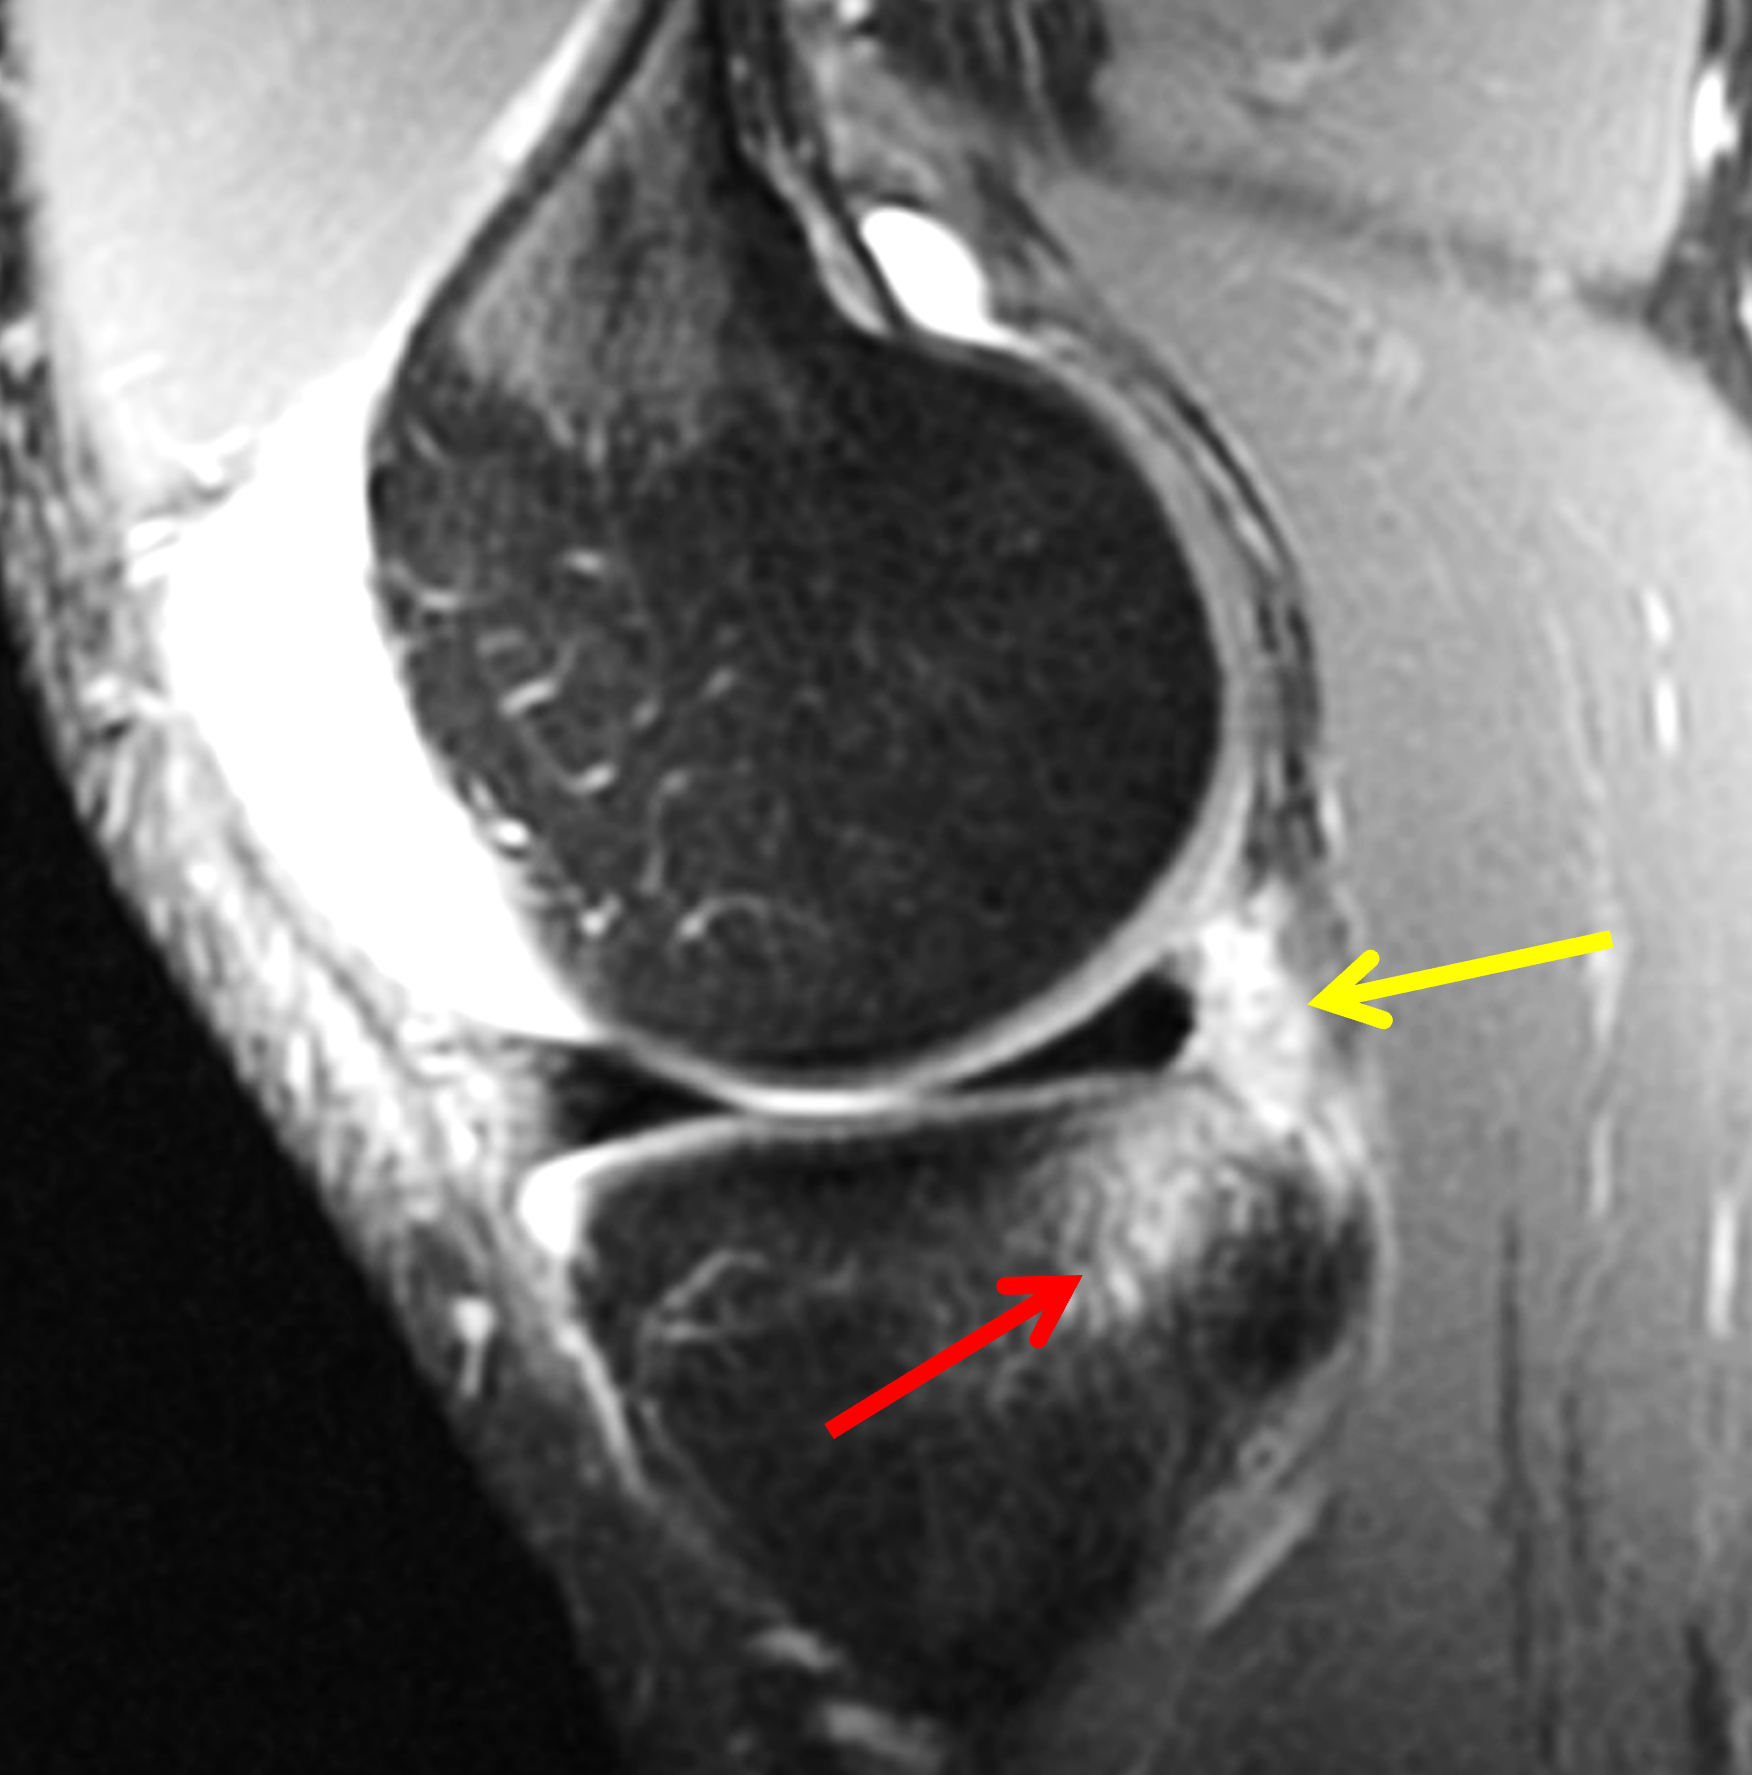

A 19-year-old collegiate baseball player sustained a twisting injury to the knee 3 weeks earlier. Sagittal (1A) proton density-weighted fat-suppressed image through the intercondylar notch, (1B and 1C) proton density-weighted images through the medial compartment, and (1D) fat-suppressed proton density image through the medial compartment are provided. What are the findings? What is your diagnosis?

Figure 2: (2A) Sagittal image through the intercondylar notch shows a complete tear of the anterior cruciate ligament (arrowheads). (2B and 2C) Near the posterior meniscocapsular junction of the medial meniscus, there is disruption of the posterior meniscotibial ligament (red arrow) and irregularity of the posterior meniscocapsular ligament (yellow arrow). (2D) On the fluid-sensitive sequence, linear high signal intensity is interposed between the ligaments and the posterior horn of the medial meniscus (arrowheads).

Anterior cruciate ligament tear with a medial meniscal ramp lesion.